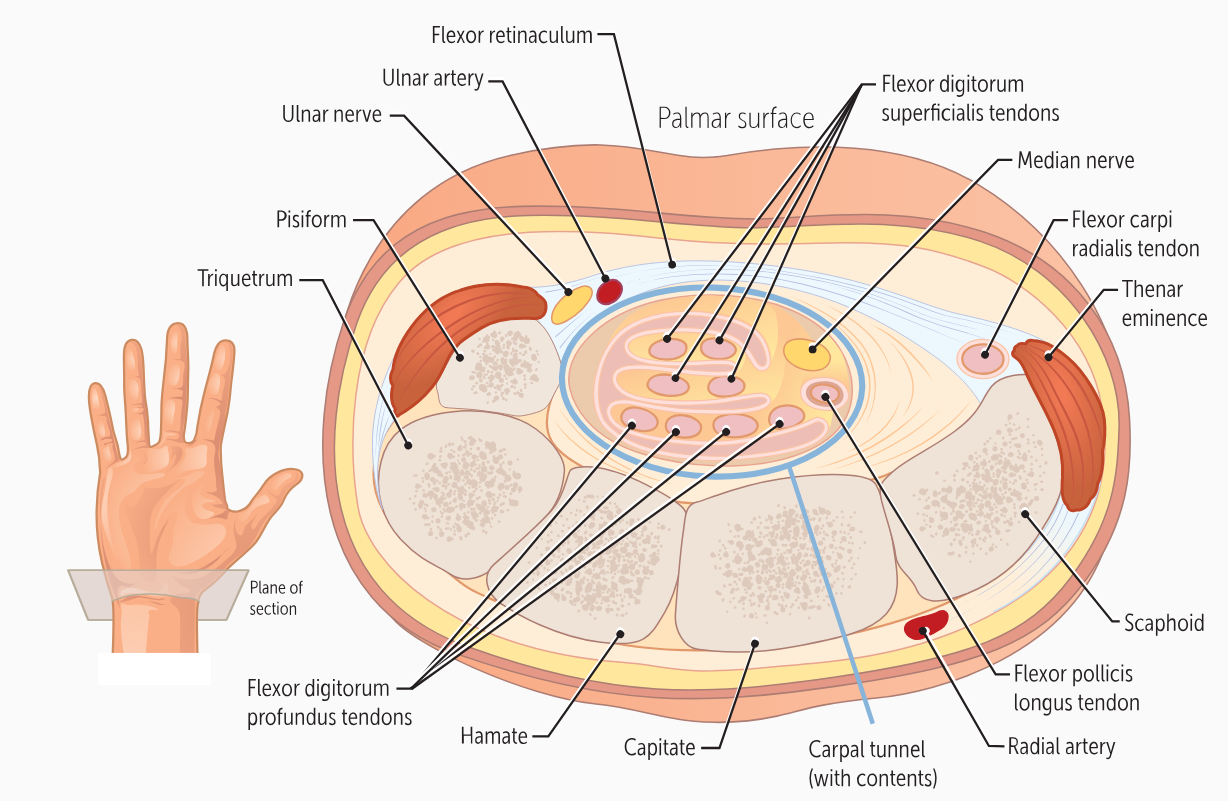

The carpals form the floor of a “tunnel” covered by a ligament called the ______________. This carpal tunnel allows tendons, nerves, and blood vessels to cross the wrist and enter the hand.

flexor retinaculum